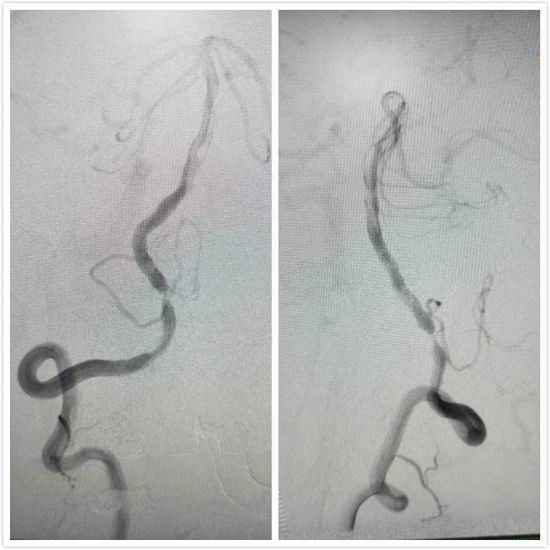

经充分准备后,由北京天坛医院介入科高峰主任与神经内科介入团队于全麻下为赵大爷行了右侧椎动脉球囊扩张+支架成形术,手术过程非常顺利,支架置入后,患者血管狭窄处管径恢复正常,血流通畅,术后未出现并发症,患者恢复良好。

赵大爷术后照片